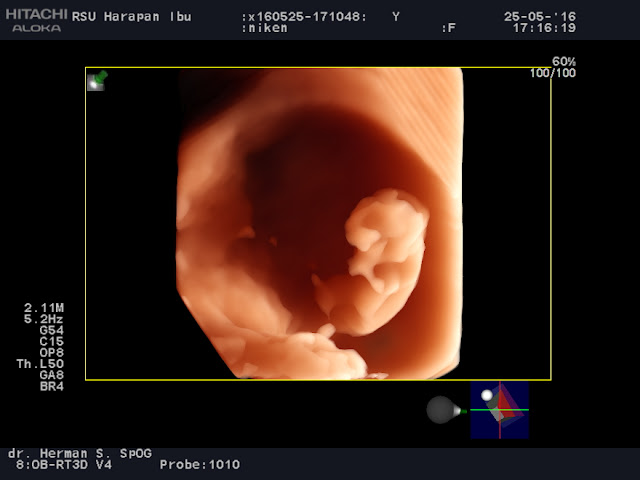

Berikut hasil pemeriksaan dengan menggunakan USG 4 Dimensi :